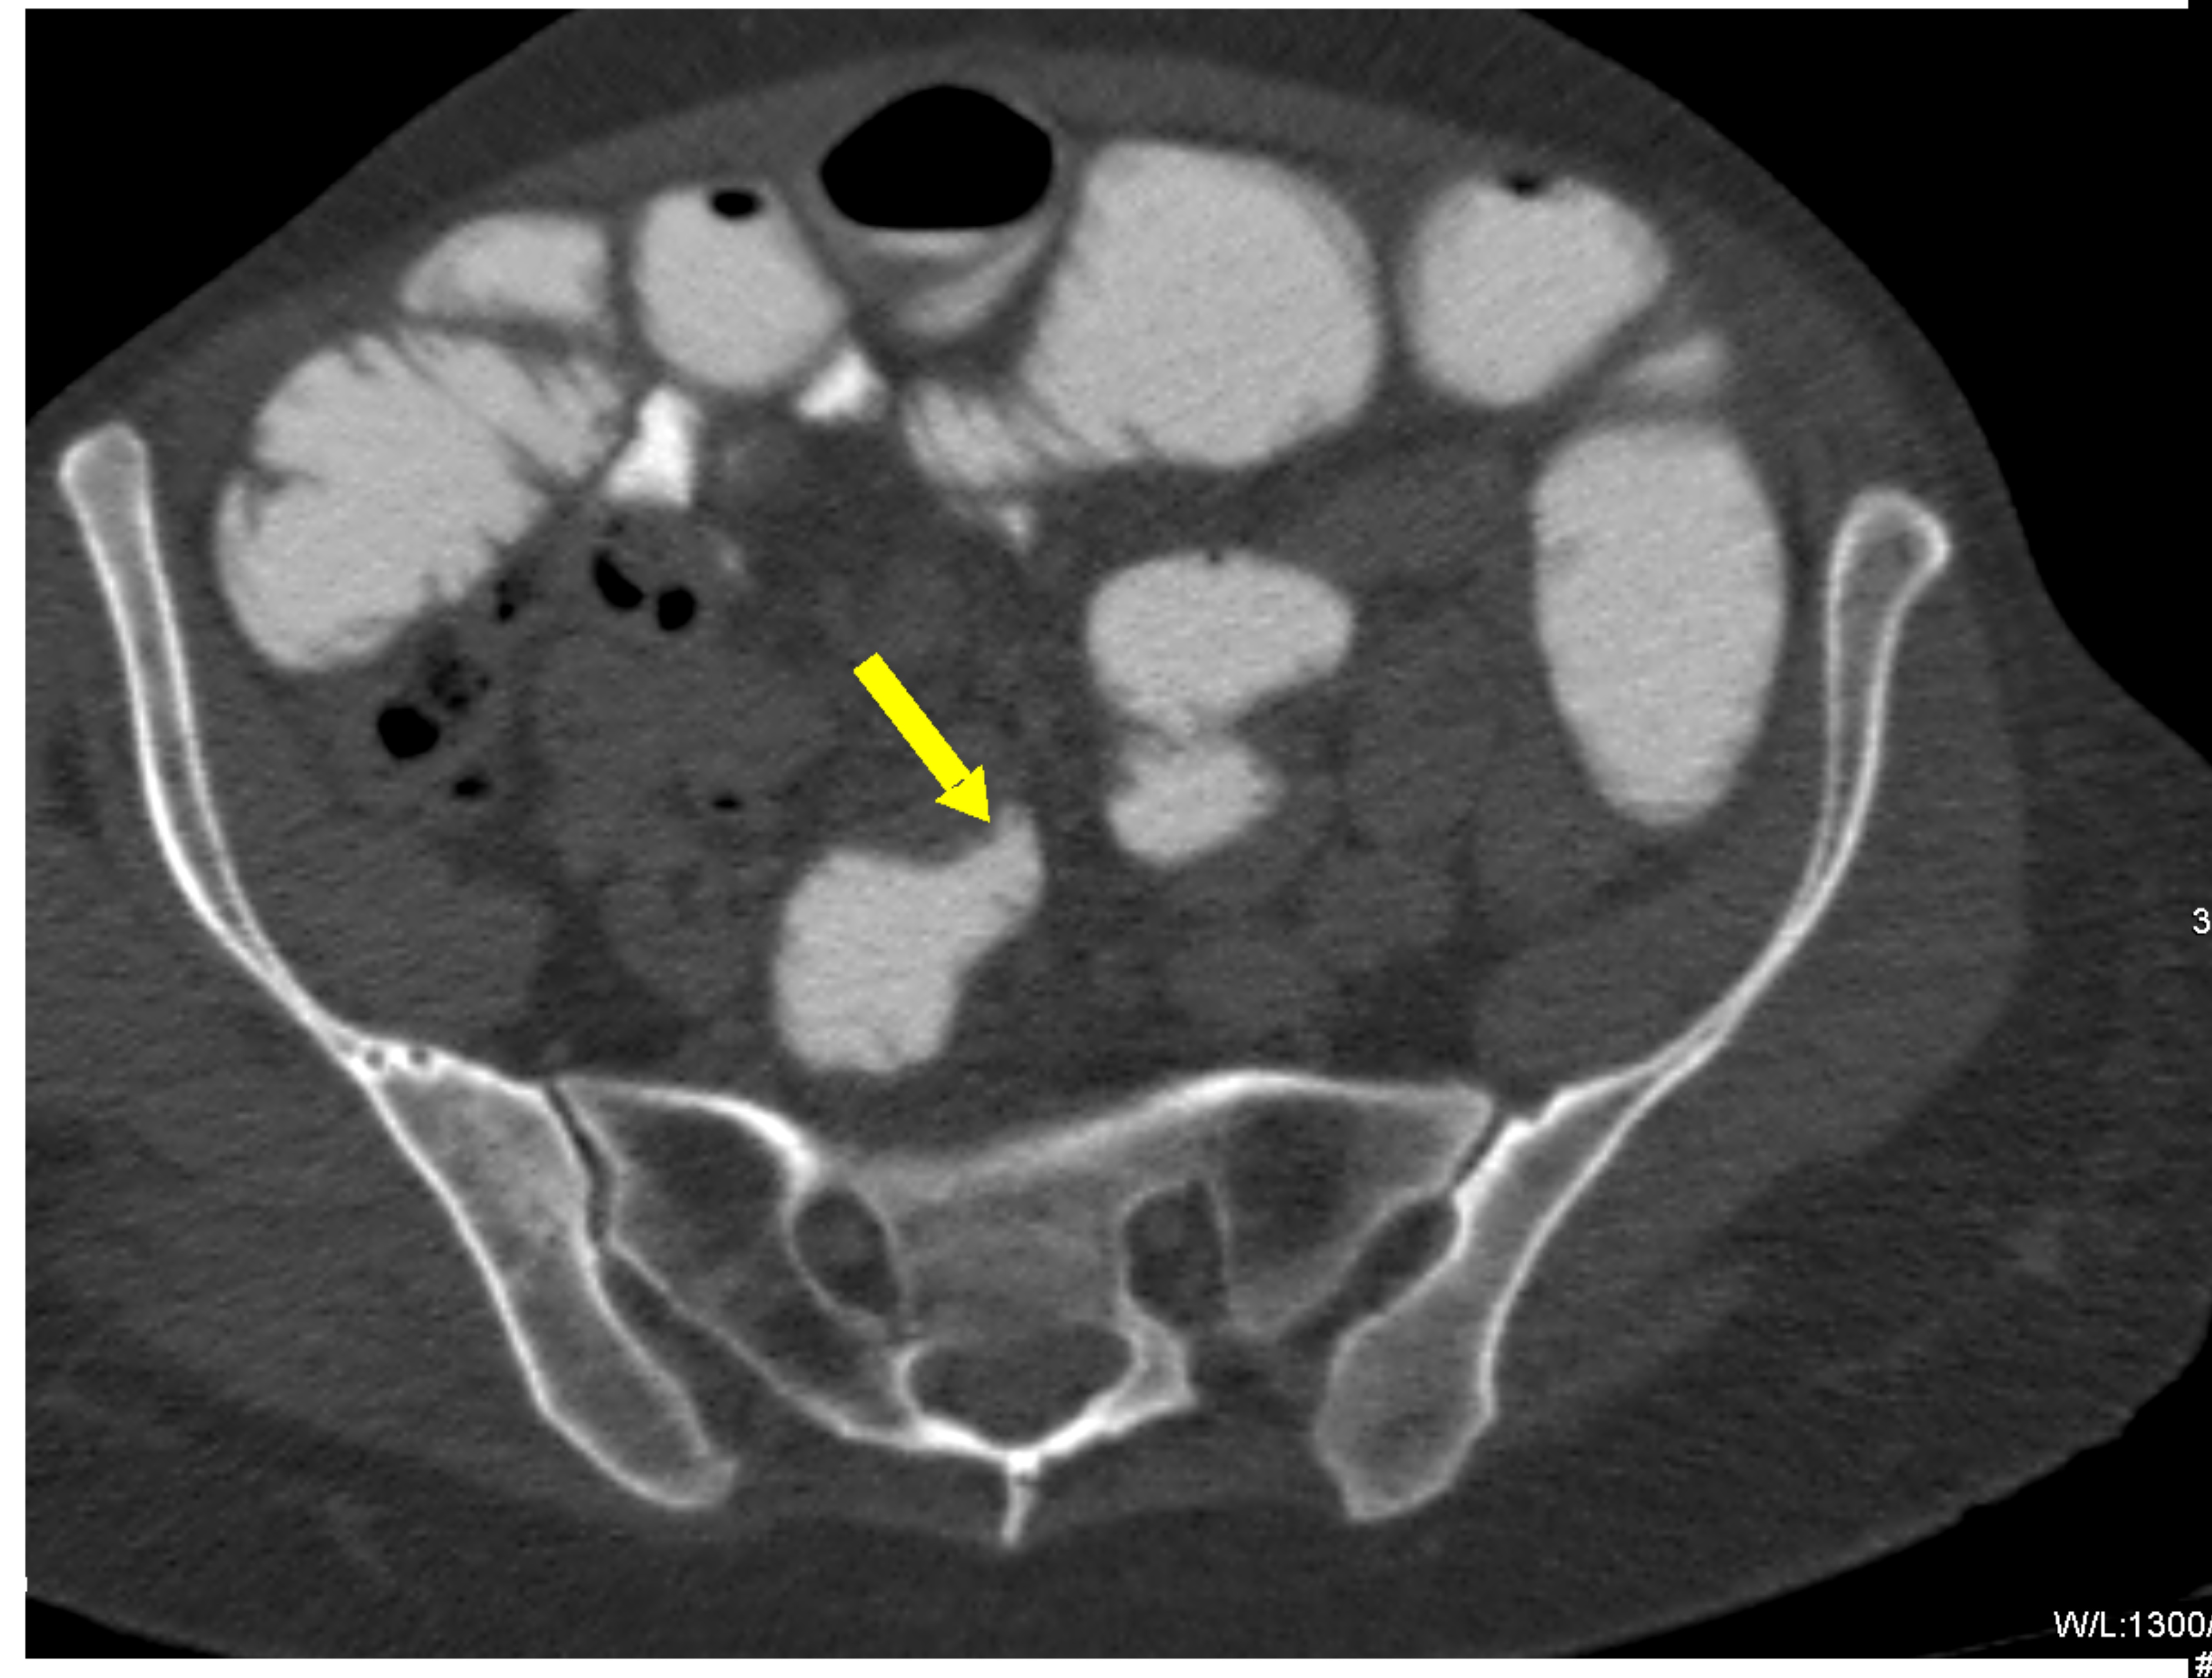

Small bowel obstruction is a common clinical presentation that presents a diagnostic conundrum. Over the last 2 decades, there has been a paradigm shift in the radiological investigation of small bowel obstruction (SBO) and in the indication for and timing of surgical intervention. Cross sectional imaging (predominantly computed tomography) has largely replaced the widespread use of radiographic small bowel follow-through studies as the imaging modality of choice for SBO. This article illustrates the current imaging modalities available for diagnosis of small bowel obstruction. (Full text available online at www.medpharm.tandfonline.com/ojfp) S Afr Fam Pract 2015; DOI: /10.1080/20786190.2014.977052